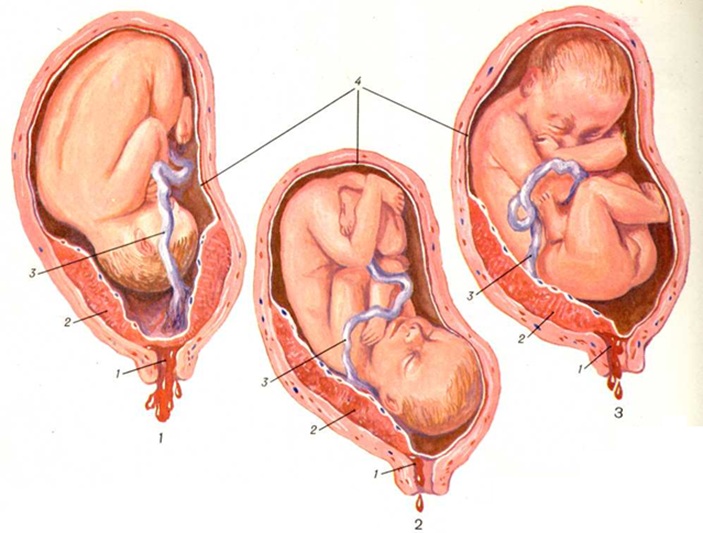

Околоплодный пузырь и плацента: структура и функции